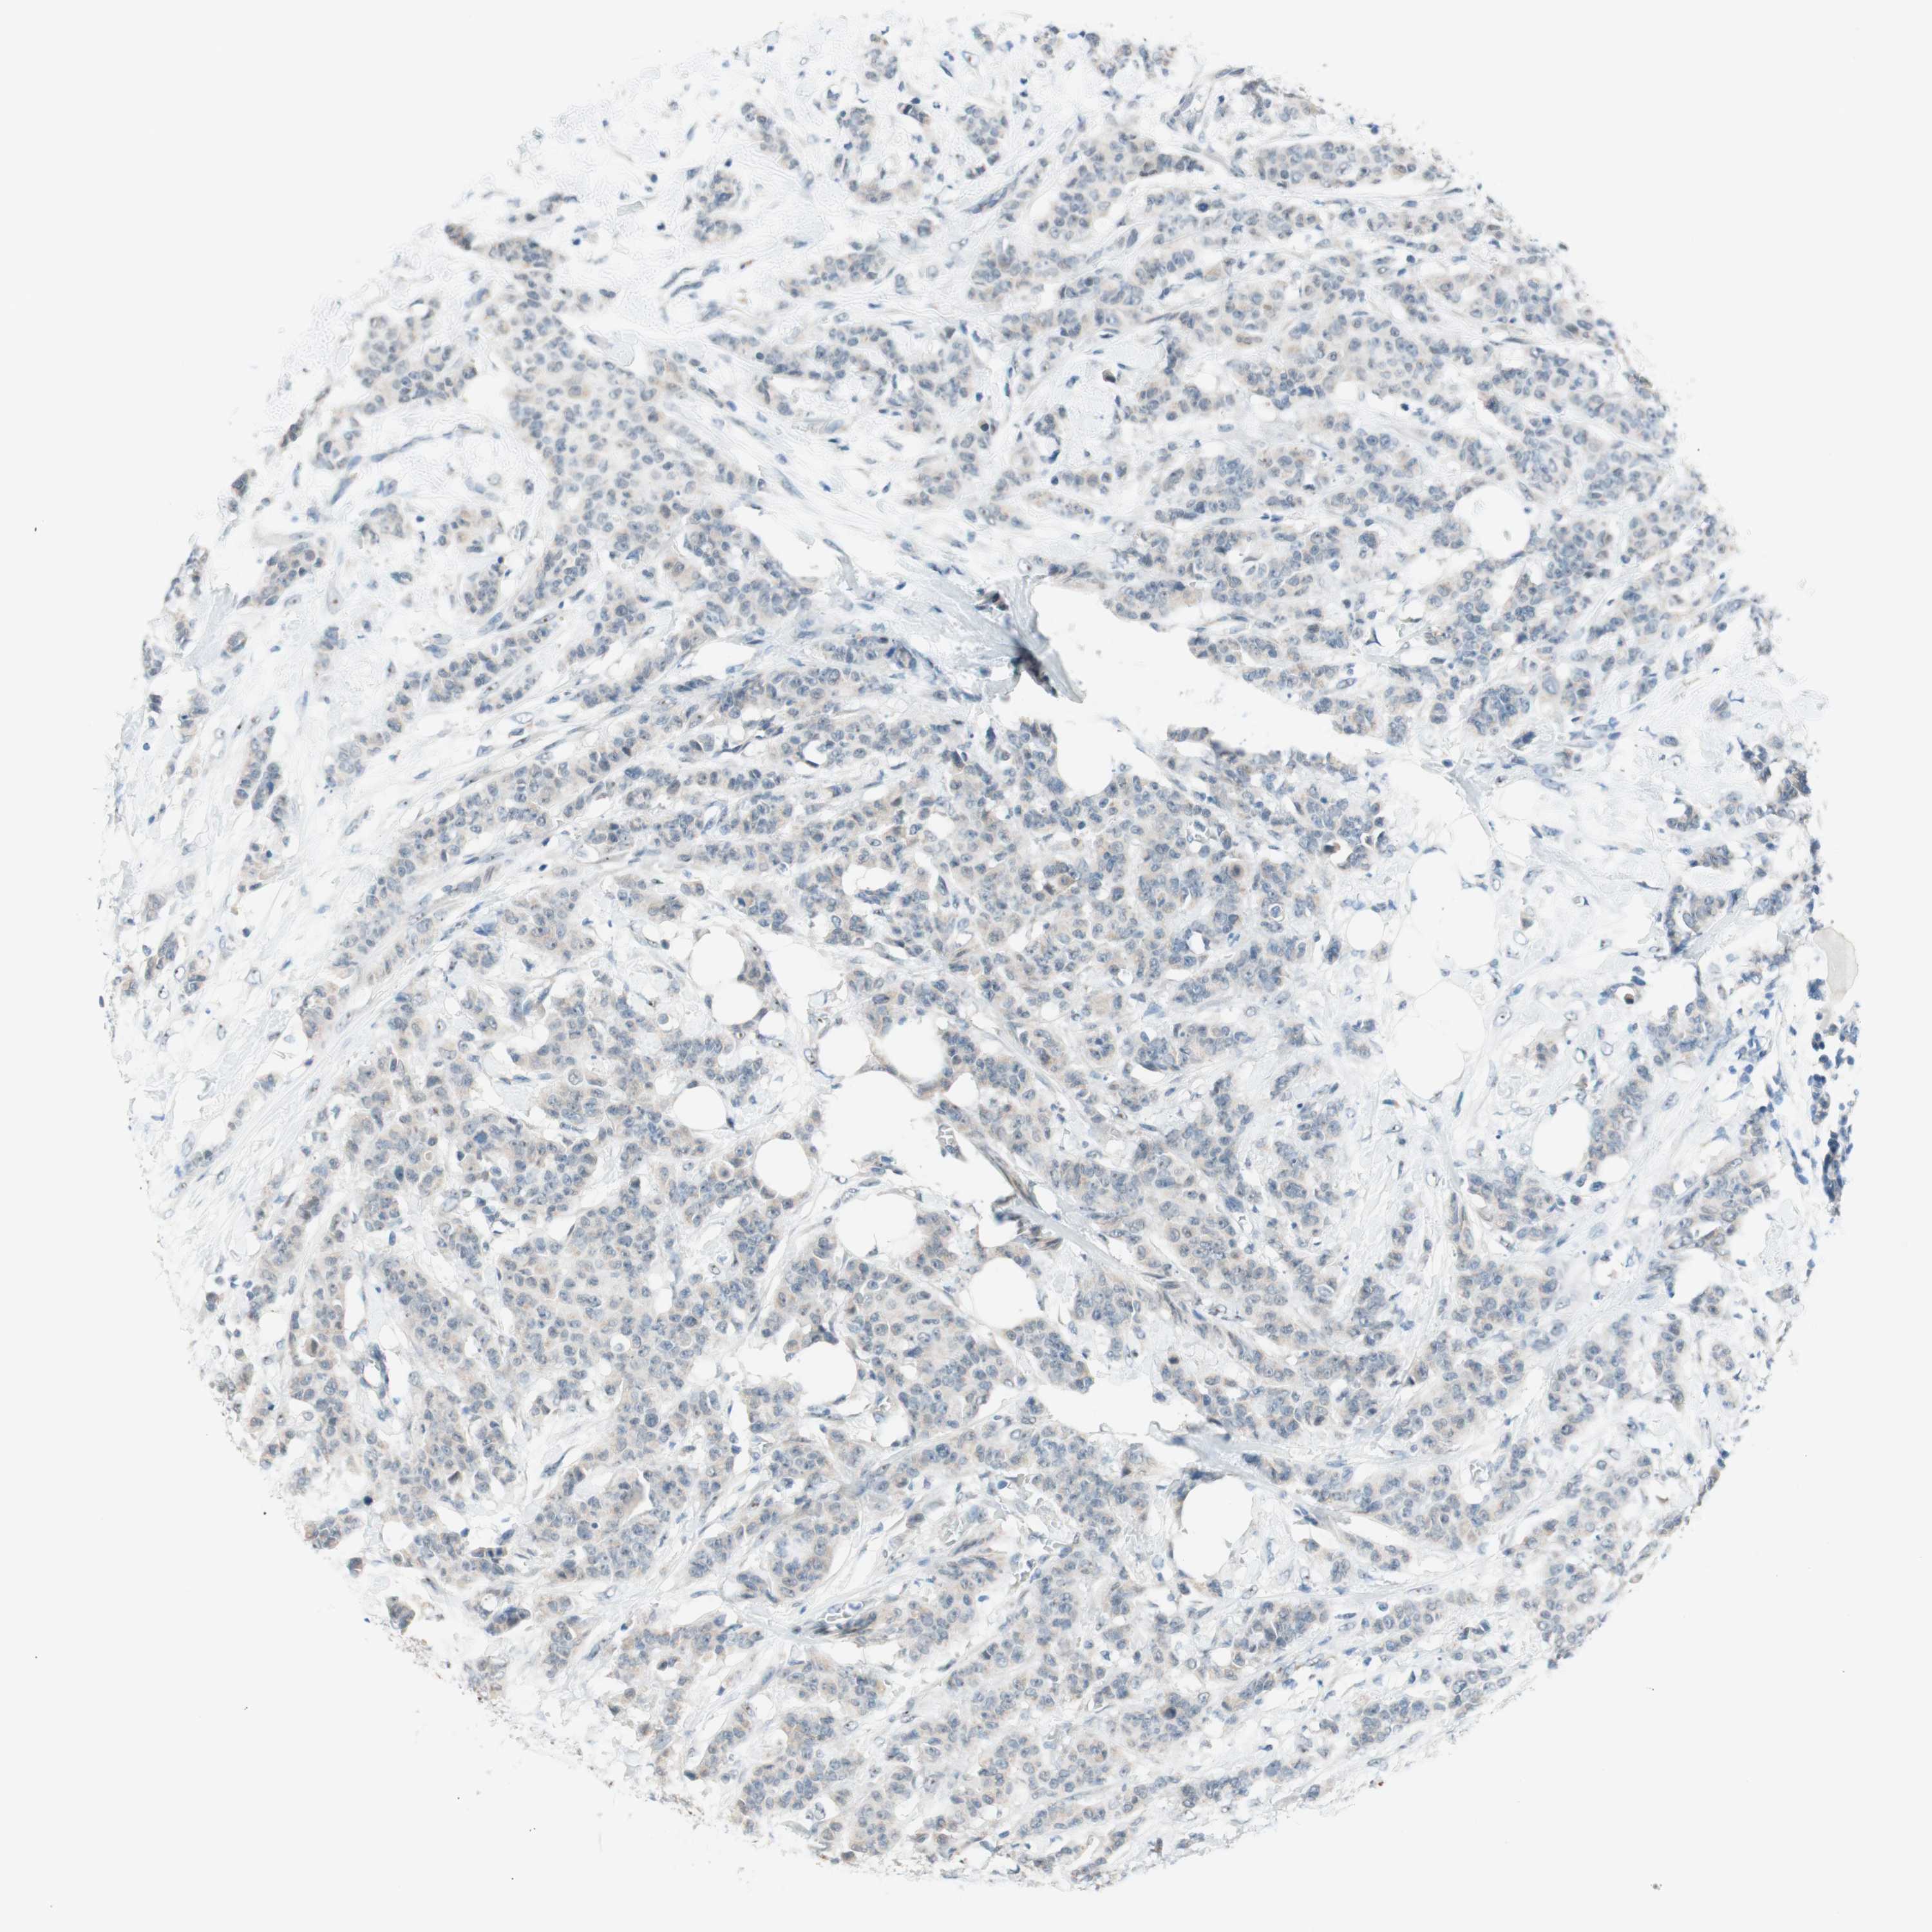

CANCER BREAST CANCER Show tissue menu

BRCA TCGA BRCA VALIDATION PROTEIN EXPRESSION